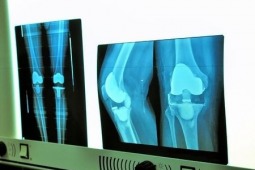

Analiza dotyczyła populacji Stanów Zjednoczonych. Późniejszy wiek wykonywania tych zabiegów w populacji chorych na mizs i SpA, jest pośrednio wskaźnikiem postępu leczenia farmakologicznego na przestrzeni lat, pozwalającego na skuteczne zahamowanie aktywności choroby i zapobieżenie nieodwracalnym destrukcjom kostnym. Badacze przeanalizowali narodowe bazy danych w okresie 1991-2005, gromadząc dane o ponad 2,800 mln zabiegów artroplastyki stawu kolanowego, biodrowego i ramiennego. We wspomnianym okresie częstość zabiegów wzrosła blisko dwukrotnie wśród chorych z niezapalnymi chorobami stawów (124,5/100tys. (1991) vs 247,5/100tys. (2005)), z zauważalnym spadkiem wieku wykonywania zabiegów, podczas gdy w przypadku zapaleń stawów pozostała na stabilnym poziomie (5,1/100tys.). W grupie chorych na rzs i niezapalne artropatie najczęściej wykonywanym zabiegiem była artroplastyka stawu kolanowego, natomiast wśród chorych na mizs i SpA - stawu biodrowego. Jak wskazują dane w części przypadków chorzy na rzs są poddani artroplastyce z powodu wtórnej choroby zwyrodnieniowej stawów, za czym przemawiać może wyraźniejszy spadek częstości zabiegów artroplastyki u młodszych chorych, niż w starszych grupach wiekowych. Wśród chorych na mizs zaobserwowano większą tendencję spadkową zabiegów operacyjnych w populacji męskiej, niż u kobiet - wg badań płeć żeńska uważana jest za czynnik prognostyczny złej odpowiedzi na leczenie.